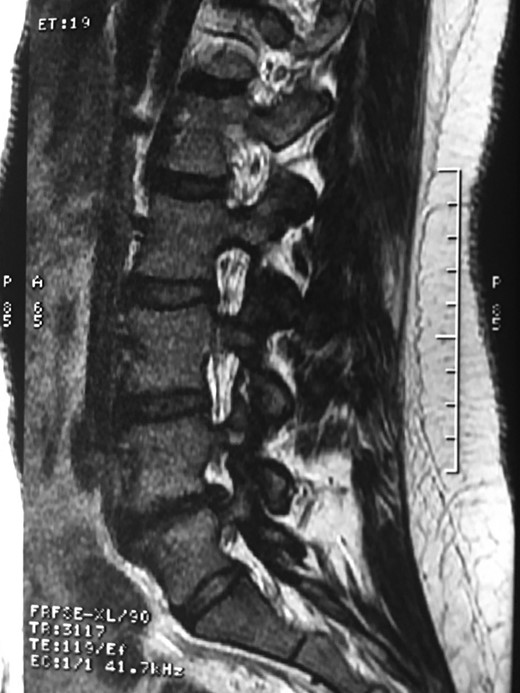

A 42-year-old female presented to the clinic with a history of chronic low back pain. She reported no relevant medical history. She had already been treated in the last 4 years by general practitioners with analgesics and home based physiotherapy with no satisfactory results. She had two previous admissions to the emergency department where morphine was prescribed to control the pain on her lower back. She was under ambulatory treatment with diclofenac, and tizanidine with partial relief of symptoms. Her main complaint was pain on the lower lumbar back with no radiation to the lower extremities. In her physical evaluation she presented limitation to full rotation and bending of the lumbar spine due to pain. Lasegue sign was negative, sensitivity, reflexes, sagittal balance, distal muscular strength and pulses were normal. Radiographs showed an overdeveloped left transverse process of the fifth lumbar vertebra which contacts with the sacrum at the left sacral wing with signs of degeneration at the same site (Fig. 1). Magnetic resonance imaging (MRI) studies were obtained (Figs 2–5). The patient was taken to the operating room where infiltration with 1 mL of lidocaine and 40 mg of Triamcinolone was performed in the pseudoarticulation between the left transverse process and the sacrum under fluoroscopic guidance. She reported a complete relief of pain after the procedure. At three months follow-up she was managed with strengthening and stabilizing exercises for the lumbar spine and postural education was initiated. She remains asymptomatic at her 12 months follow up.

Degenerative changes at the facets and disc in the adjacent segment.

The partial fusion at the lower part of the lumbosacral transition produces important alterations in normal biomechanics at the levels immediately above and below the LSTV. Changes such as hypermobility and abnormal torque moments are present at the level above the LSTV, predisposing it to early degeneration (early disc pathology and facet joint degenerative disease). Restricted movement below the LSTV produces a protective effect against degeneration of disc and facets and is related to changes (facets are smaller and coronally oriented) in the dimensions of the lower level facet joints [7]. These alterations can be verified in the adjacent levels of the LSTV in our patient.